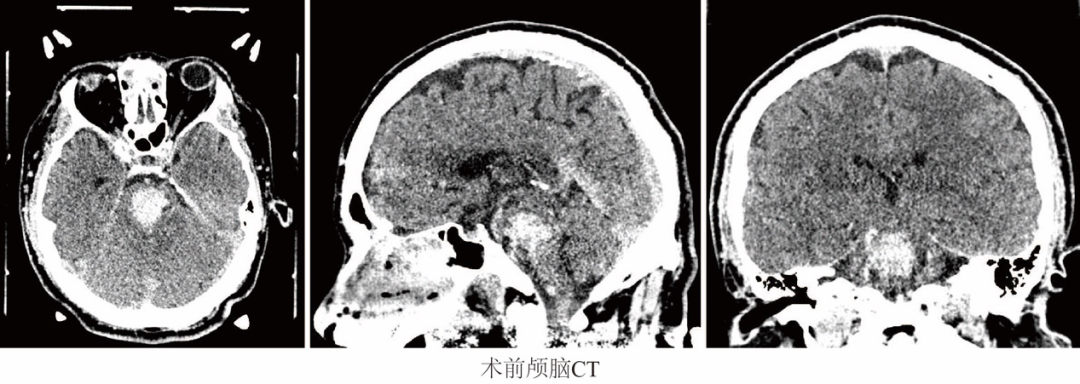

该患者为一名48岁男性,一天清晨被同事发现半躺在办公室内,于是被紧急送往珠海市人民医院。急诊行头部CT检查显示脑干出血(约8ml),病情危重,于是立即联系神经外科脑出血微创治疗团队。

当时,患者处于深昏迷状态,血压171/92mmhg,GCS评分3分,双侧瞳孔1.5mm,对光反射消失。影像学可见脑干片状高密度影,范围横穿脑干,病情非常危急,命悬一线。

手术前,在CT定位下描绘出脑干出血区域,通过计算精准测出血肿体积并制定合适的穿刺路径,避免损伤不必要的神经血管。经精准穿刺,清除颅内积血约8ml,手术仅耗时约1.5小时,术后1小时复查头颅CT,可见血肿基本清除。患者随后转入神经外科监护室继续密切观察治疗,生命体征平稳。